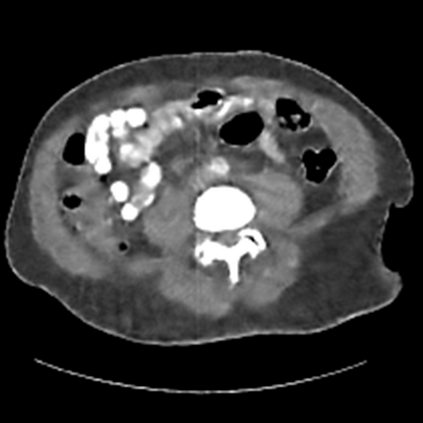

Sparse-view computed tomography (CT) -- using a small number of projections for tomographic reconstruction -- enables much lower radiation dose to patients and accelerated data acquisition. The reconstructed images, however, suffer from strong artifacts, greatly limiting their diagnostic value. Current trends for sparse-view CT turn to the raw data for better information recovery. The resultant dual-domain methods, nonetheless, suffer from secondary artifacts, especially in ultra-sparse view scenarios, and their generalization to other scanners/protocols is greatly limited. A crucial question arises: have the image post-processing methods reached the limit? Our answer is not yet. In this paper, we stick to image post-processing methods due to great flexibility and propose global representation (GloRe) distillation framework for sparse-view CT, termed GloReDi. First, we propose to learn GloRe with Fourier convolution, so each element in GloRe has an image-wide receptive field. Second, unlike methods that only use the full-view images for supervision, we propose to distill GloRe from intermediate-view reconstructed images that are readily available but not explored in previous literature. The success of GloRe distillation is attributed to two key components: representation directional distillation to align the GloRe directions, and band-pass-specific contrastive distillation to gain clinically important details. Extensive experiments demonstrate the superiority of the proposed GloReDi over the state-of-the-art methods, including dual-domain ones. The source code is available at https://github.com/longzilicart/GloReDi.